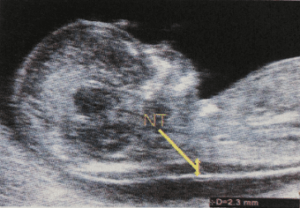

FMFについて(出生前診断)|おおのたウィメンズクリニック埼玉。インターネットホスピタル。胎児超音波診断ファントム “SPACE FAN-ST” | 京都科学。山形県庄内産 つや姫 白米5kg Gセレクション 特別栽培米。裁断済み。書き込みありです。了承の上ご購入検討ください。「胎児超音波診断」松田 義雄 / 谷垣 伸治定価: ¥ 8500#松田義雄 #松田_義雄 #谷垣伸治 #谷垣_伸治 #本 #自然/医療・薬学・健康。超音波外来|綱島クリニック|横浜市港北区の内科、婦人科、産科。。プロメテウス解剖学第三版